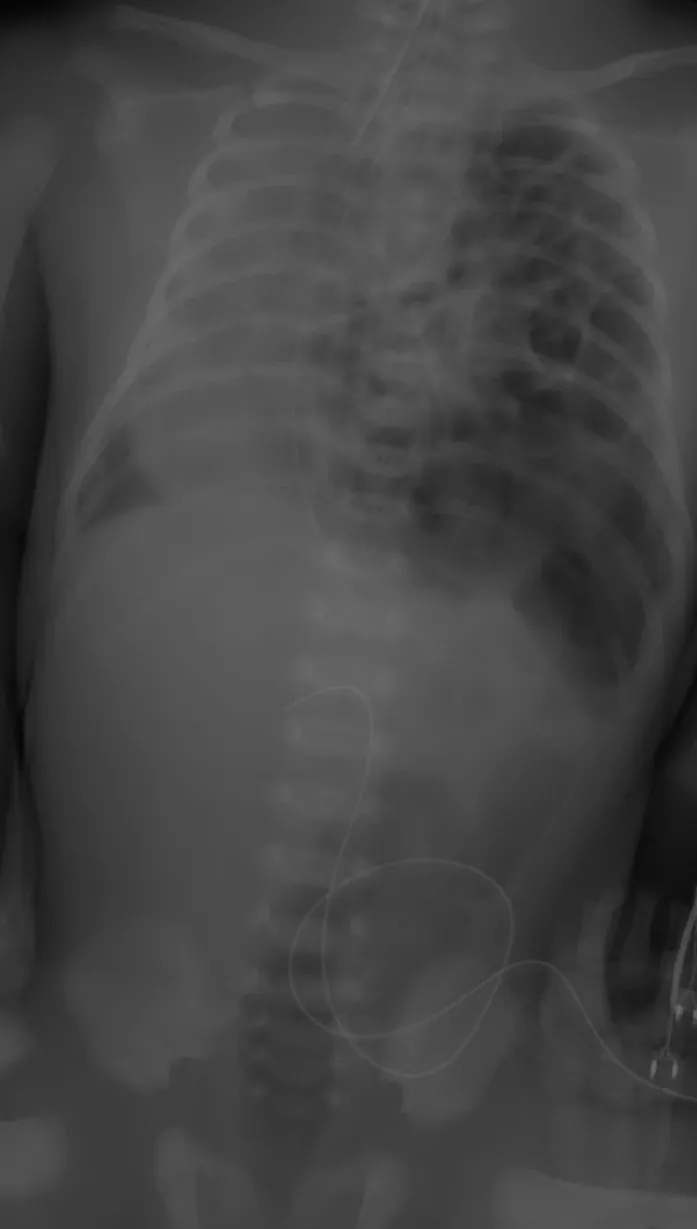

【108-2 醫學(四) 第74題】足月產新生兒因呼吸急促住進新生兒加護病房,胸腹部X光如附圖,則最可能的診斷為下列何者?

詳解

破題關鍵

這張新生兒胸腹部X光片最關鍵的線索是左側胸腔內出現了多個氣體填充的腸道影像,同時心臟和縱膈腔被推擠到右側,這明確指向橫膈疝脫。

選項拆解